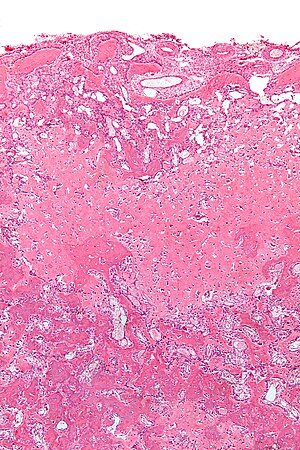

Osteoblastoma. H&E stain. | |

| LM | anastomosing bony trabeculae with variable mineralization, osteoblastic rimming, no nuclear atypia of osteocytes |

| LM DDx | osteoid osteoma, osteosarcoma |

Microscopic

Features:[6]

- Anastomosing bony trabeculae with:

- Osteoblastic rimming.

- Cells line-up at edge of bone.

- Histomorphologically near identical/indistinguishable from osteoid osteoma.[5]